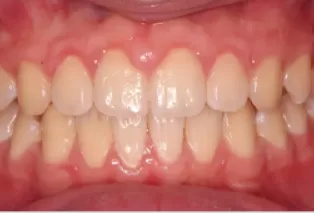

Photos intra-orales